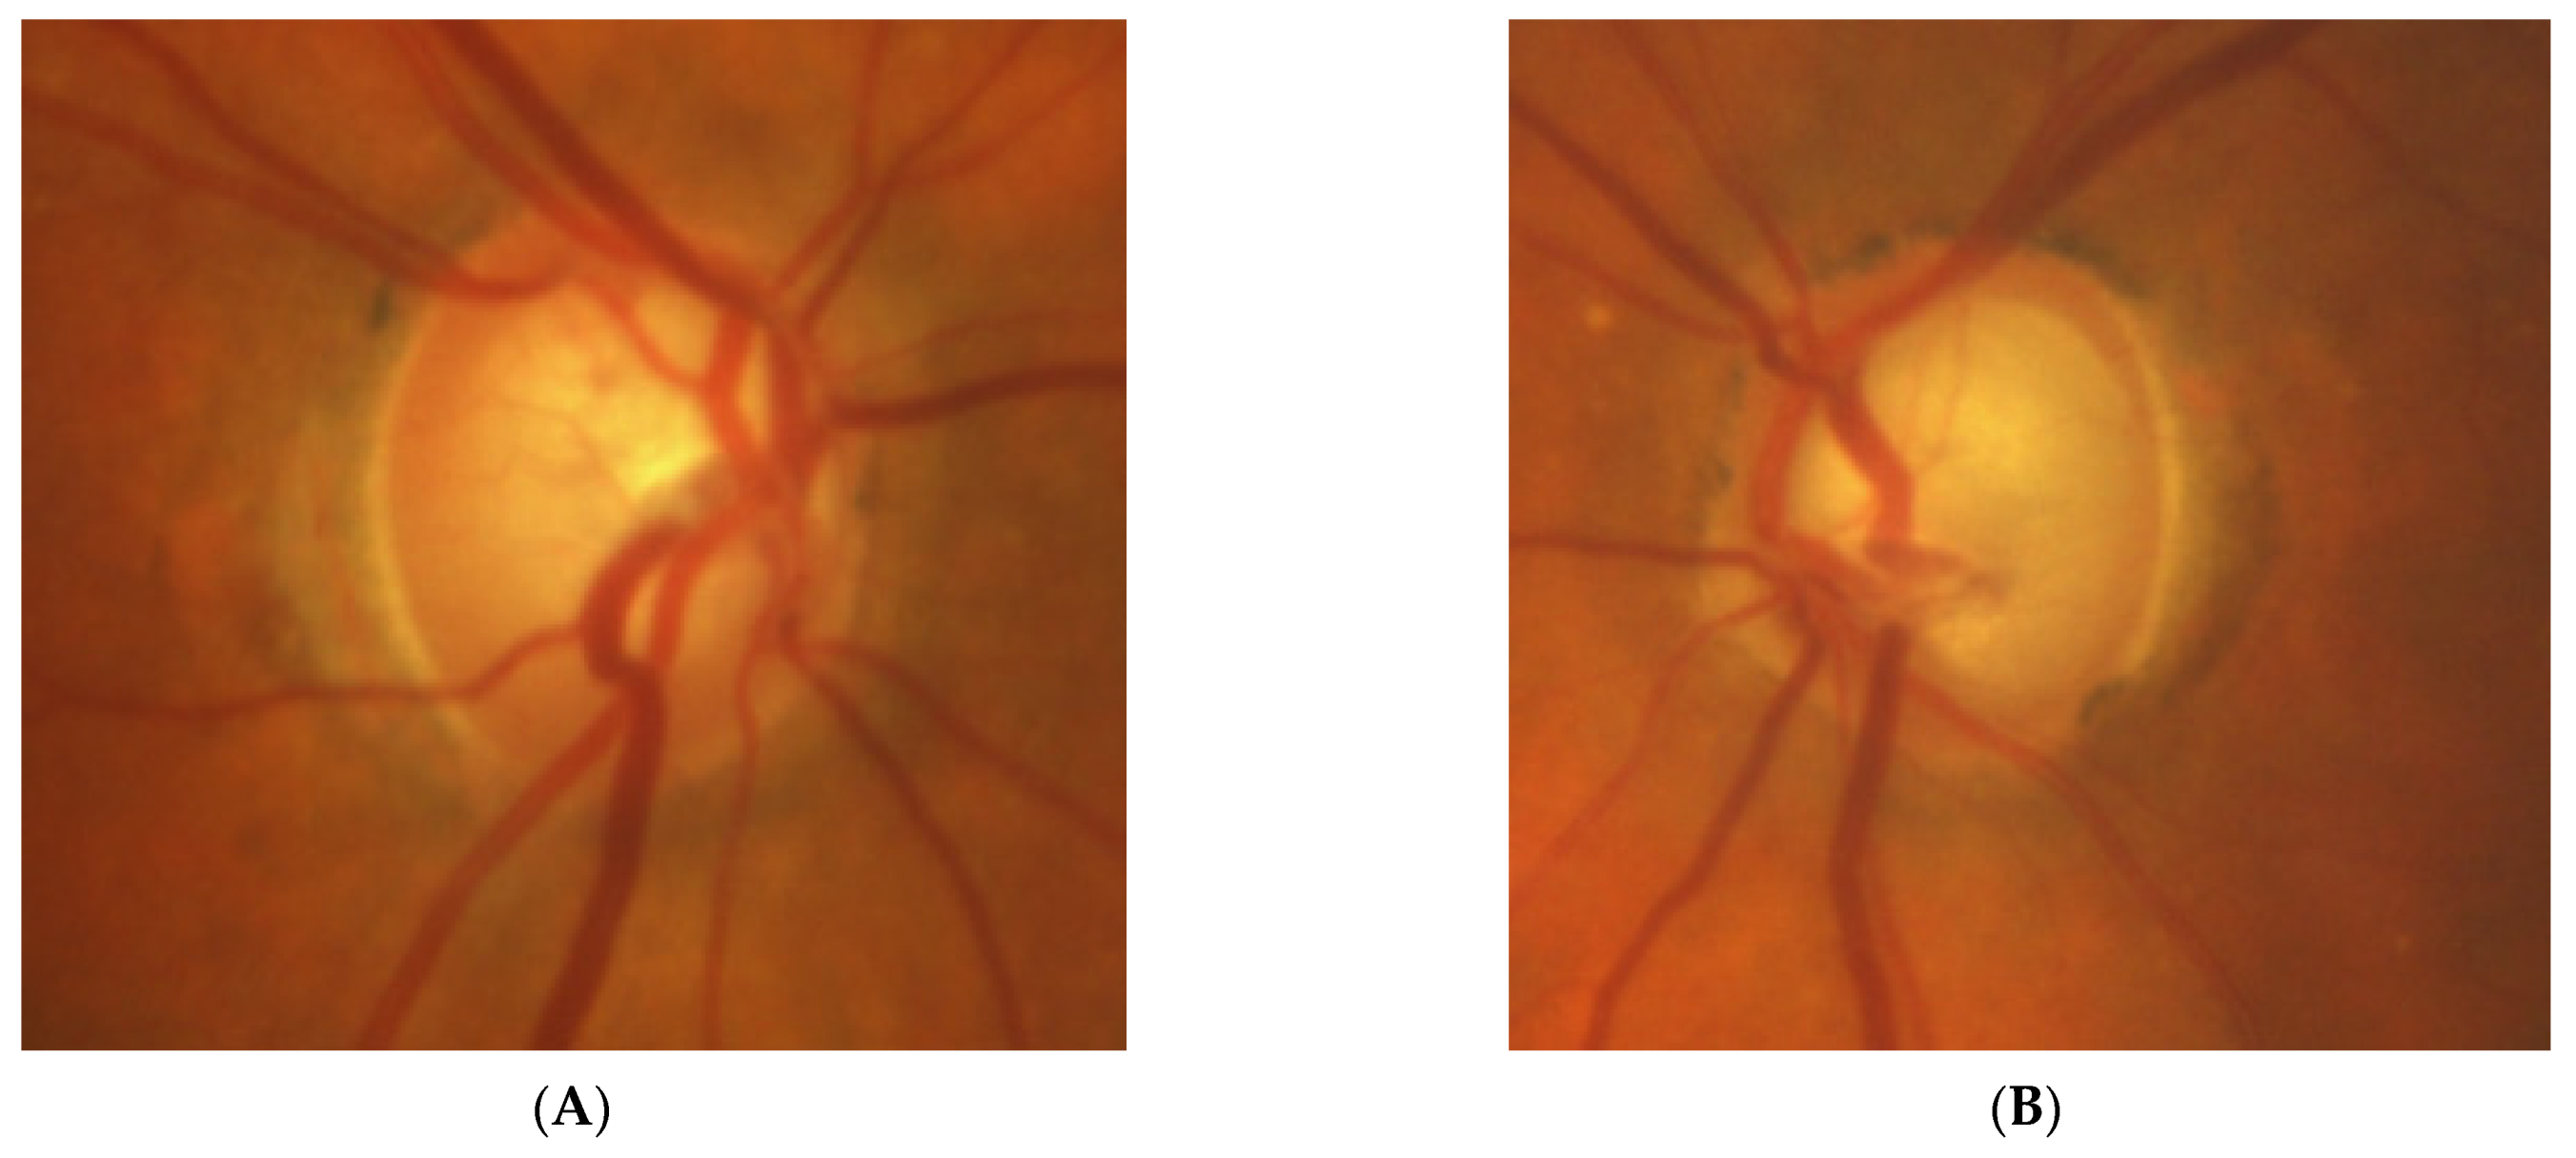

2.5. Case 5

- Lesions developing in association with an optic nerve develop unilaterally and are characterized by optic disc pallor, VF defects, and OCT findings (their morphology may differ from classical glaucomatous defects).

3.2. Glaucomatologist Perspective